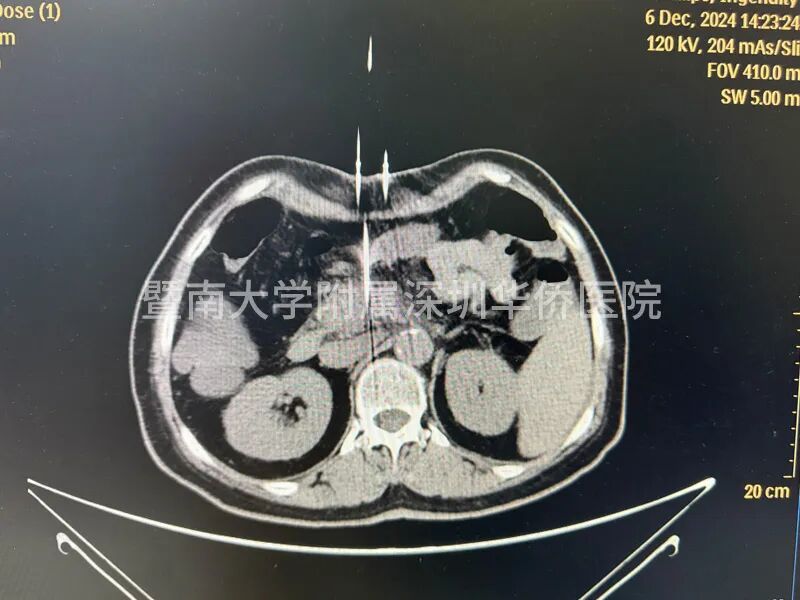

李女土的肿瘤在胰头位置,大小为2.8*3厘米,已经包绕肠系膜上动脉,失去了手术机会,在得知广东省应用了国产纳米刀治疗手术技术后,决定不远千里来到暨南大学附属深圳华侨医院,接受纳米刀消融手术。

上午11点,李女士正式进入手术室,多位相关领域专家,通过国产研发的新型设备正式对李女士进行手术,纳米刀消融技术适合中晚期的胰腺癌的治疗,这台手术设备在产品设计中,具有全球领先的核心技术,实现了在消融过程中,电压恰到好处,作用于细胞膜磷脂双分子层,形成不可逆电穿孔,诱导细胞凋亡,激活细胞免疫,经过几个小时的奋战,李女士成功完成手术治疗,此次纳米刀消融手术,顺利开展完成!

许林锋教授介绍:“纳米刀消融技术对操作者要求较高,与我们传统的消融手术也不同,以前的消融手术一个针就可以了,放到肿瘤的中心的部位,而纳米刀消融最少要有2根针,它是利用两个电极针之间的放电,就是一个公分的距离,可能有2-3千伏电压,所以说对电极针的定位非常重要。”

2、精准可控:在超声或CT引导下,纳米刀治疗系统能够精确计算出消融区域的形状和体积,并告知探针的有效消融范围。治疗计划精确到毫米级别,为患者提供个性化的治疗方案。

治疗效果:纳米刀治疗后,显微镜下可见治疗区域和非治疗区域界限清晰。直径大于一毫米的血管、主要血管和导管均不受影响,继续维持正常功能。治疗后1-3个月,通过CT扫描几乎看不到治疗痕迹。